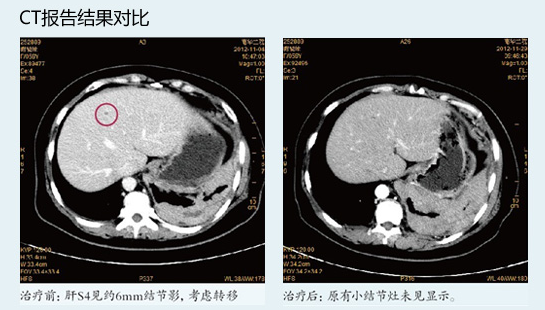

通过“WB-1无创全身热疗”联合化放疗等综合治疗,患者淋巴细胞、单核细胞、血小板较治疗前有明显改善并恢复至正常。肿瘤标志物CA-125、CEA虽还在异常范围,但较治疗前明显好转。流式细胞检测示患者体内T细胞亚群有一定程度的改善。治疗前后CT比较(见下图),提示患者肝S4约6mm结节影(转移灶)消失;